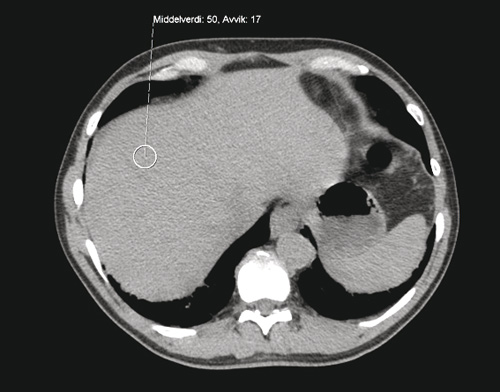

Rettelse En kvinne i 70-årene med redusert allmenntilstand, dyspné og utbredte smerter Kiarash Tazmini, Heidi Nygaard Bakken, Fredrik Hellem Schjesvold Om forfatterne Se alle artikler Kiarash Tazmini Se alle artikler Heidi Nygaard Bakken Se alle artikler Fredrik Hellem Schjesvold () sporsmal_grey_rgb Artikkel Tidsskr Nor Legeforen 2012; 132: 1969 – 72 I Tidsskriftet nr. 17/2012, side 1971 er det feil bilde i figur 3. Her viser vi både figur 2 og riktig figur 3. Figur 2 CT abdomen uten kontrastmiddel fra pasient uten patologiske forandringer Figur 3 CT abdomen uten kontrastmiddel. Bildet viser høy attenuasjon i lever, som ved jernavleiring (dette til sammenlikning med figur 2) Vi beklager feilen, den er rettet i nettutgaven. Kommentarer ( 0 ) Dette kommentarfeltet modereres, men kommentarer blir ikke redaksjonelt behandlet ut over å sikre at de følger retningslinjer for vårt kommentarfelt. Denne artikkelen ble publisert for mer enn 12 måneder siden, og vi har derfor stengt for nye kommentarer. Publisert: 30. oktober 2012 Utgave 20, 30. oktober 2012 Tidsskr Nor Legeforen 30. oktober 2012 doi: 10.4045/tidsskr.12.1152 Opphavsrett: ©️️ Tidsskriftet 2026 PlumX 132 : 2260 Publisert: 30. oktober 2012 Utgave 20, 30. oktober 2012 Tidsskr Nor Legeforen 2012 132 : 2260 doi: 10.4045/tidsskr.12.1152 Opphavsrett: ©️️ Tidsskriftet 2026 Plum Print visual indicator of research metrics PlumX Metrics PDF Får du ikke vist PDF-filen eller vil lagre filen, kan du høyreklikke på PDF-ikonet. Velg «Lagre mål/fil som..» og hent så opp PDF-filen i for eksempel Acrobat Reader. Skriv ut Anbefalte artikler